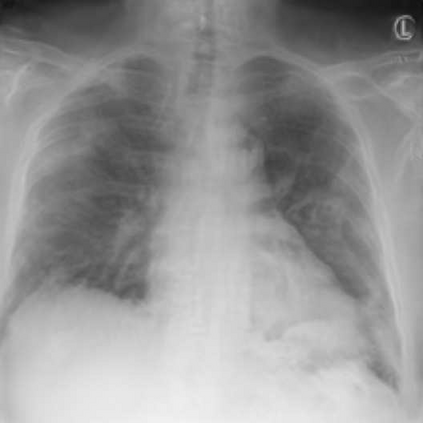

Since the beginning of the COVID-19 pandemic, researchers have developed deep learning models to classify COVID-19 induced pneumonia. As with many medical imaging tasks, the quality and quantity of the available data is often limited. In this work we train a deep learning model on publicly available COVID-19 image data and evaluate the model on local hospital chest X-ray data. The data has been reviewed and labeled by two radiologists to ensure a high quality estimation of the generalization capabilities of the model. Furthermore, we are using a Generative Adversarial Network to generate synthetic X-ray images based on this data. Our results show that using those synthetic images for data augmentation can improve the model's performance significantly. This can be a promising approach for many sparse data domains.